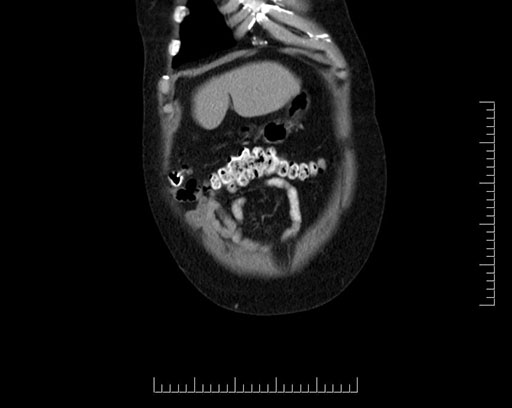

Coronal - stented